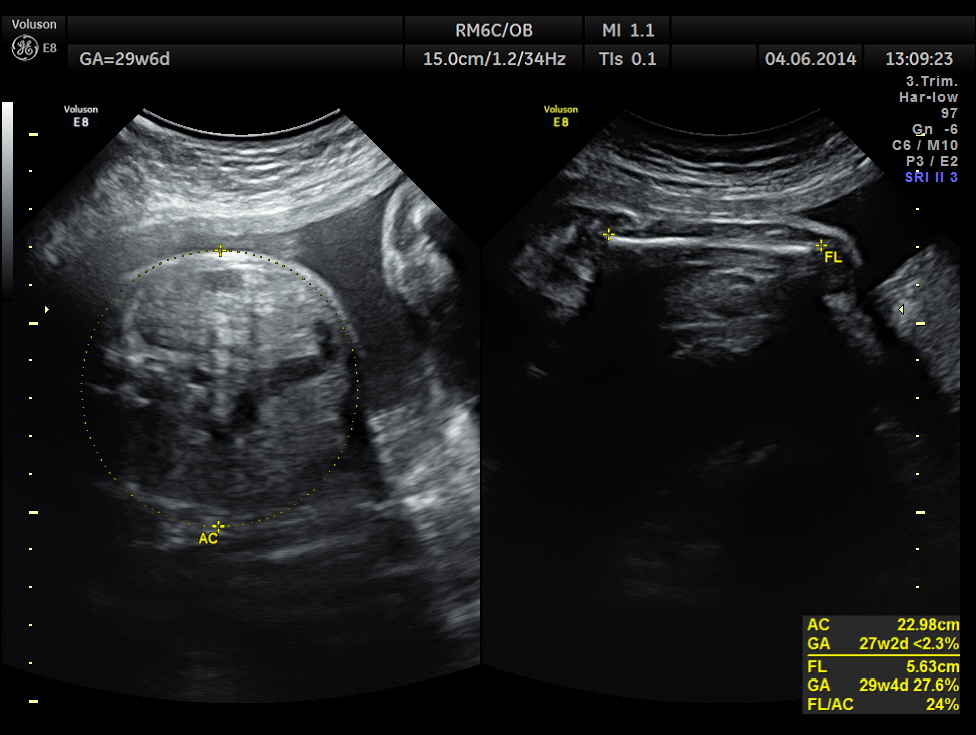

Biometric measurements show AC <2.3 %TILE

BPD , HC <10 % tile and AC is < 2.3 % tile .